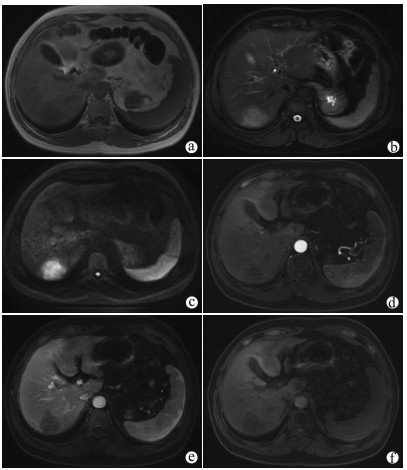

A case of huge intrahepatic biliary papillomatosis

Ziyue WANG, Daqun LIU, Jiaao YU, Jingxuan ZHANG, Guoyue LYU

2021, 37(11): 2651-2652. DOI: 10.3969/j.issn.1001-5256.2021.11.034

Abstract(810) HTML (178) PDF (2663KB)(51)

Abstract: